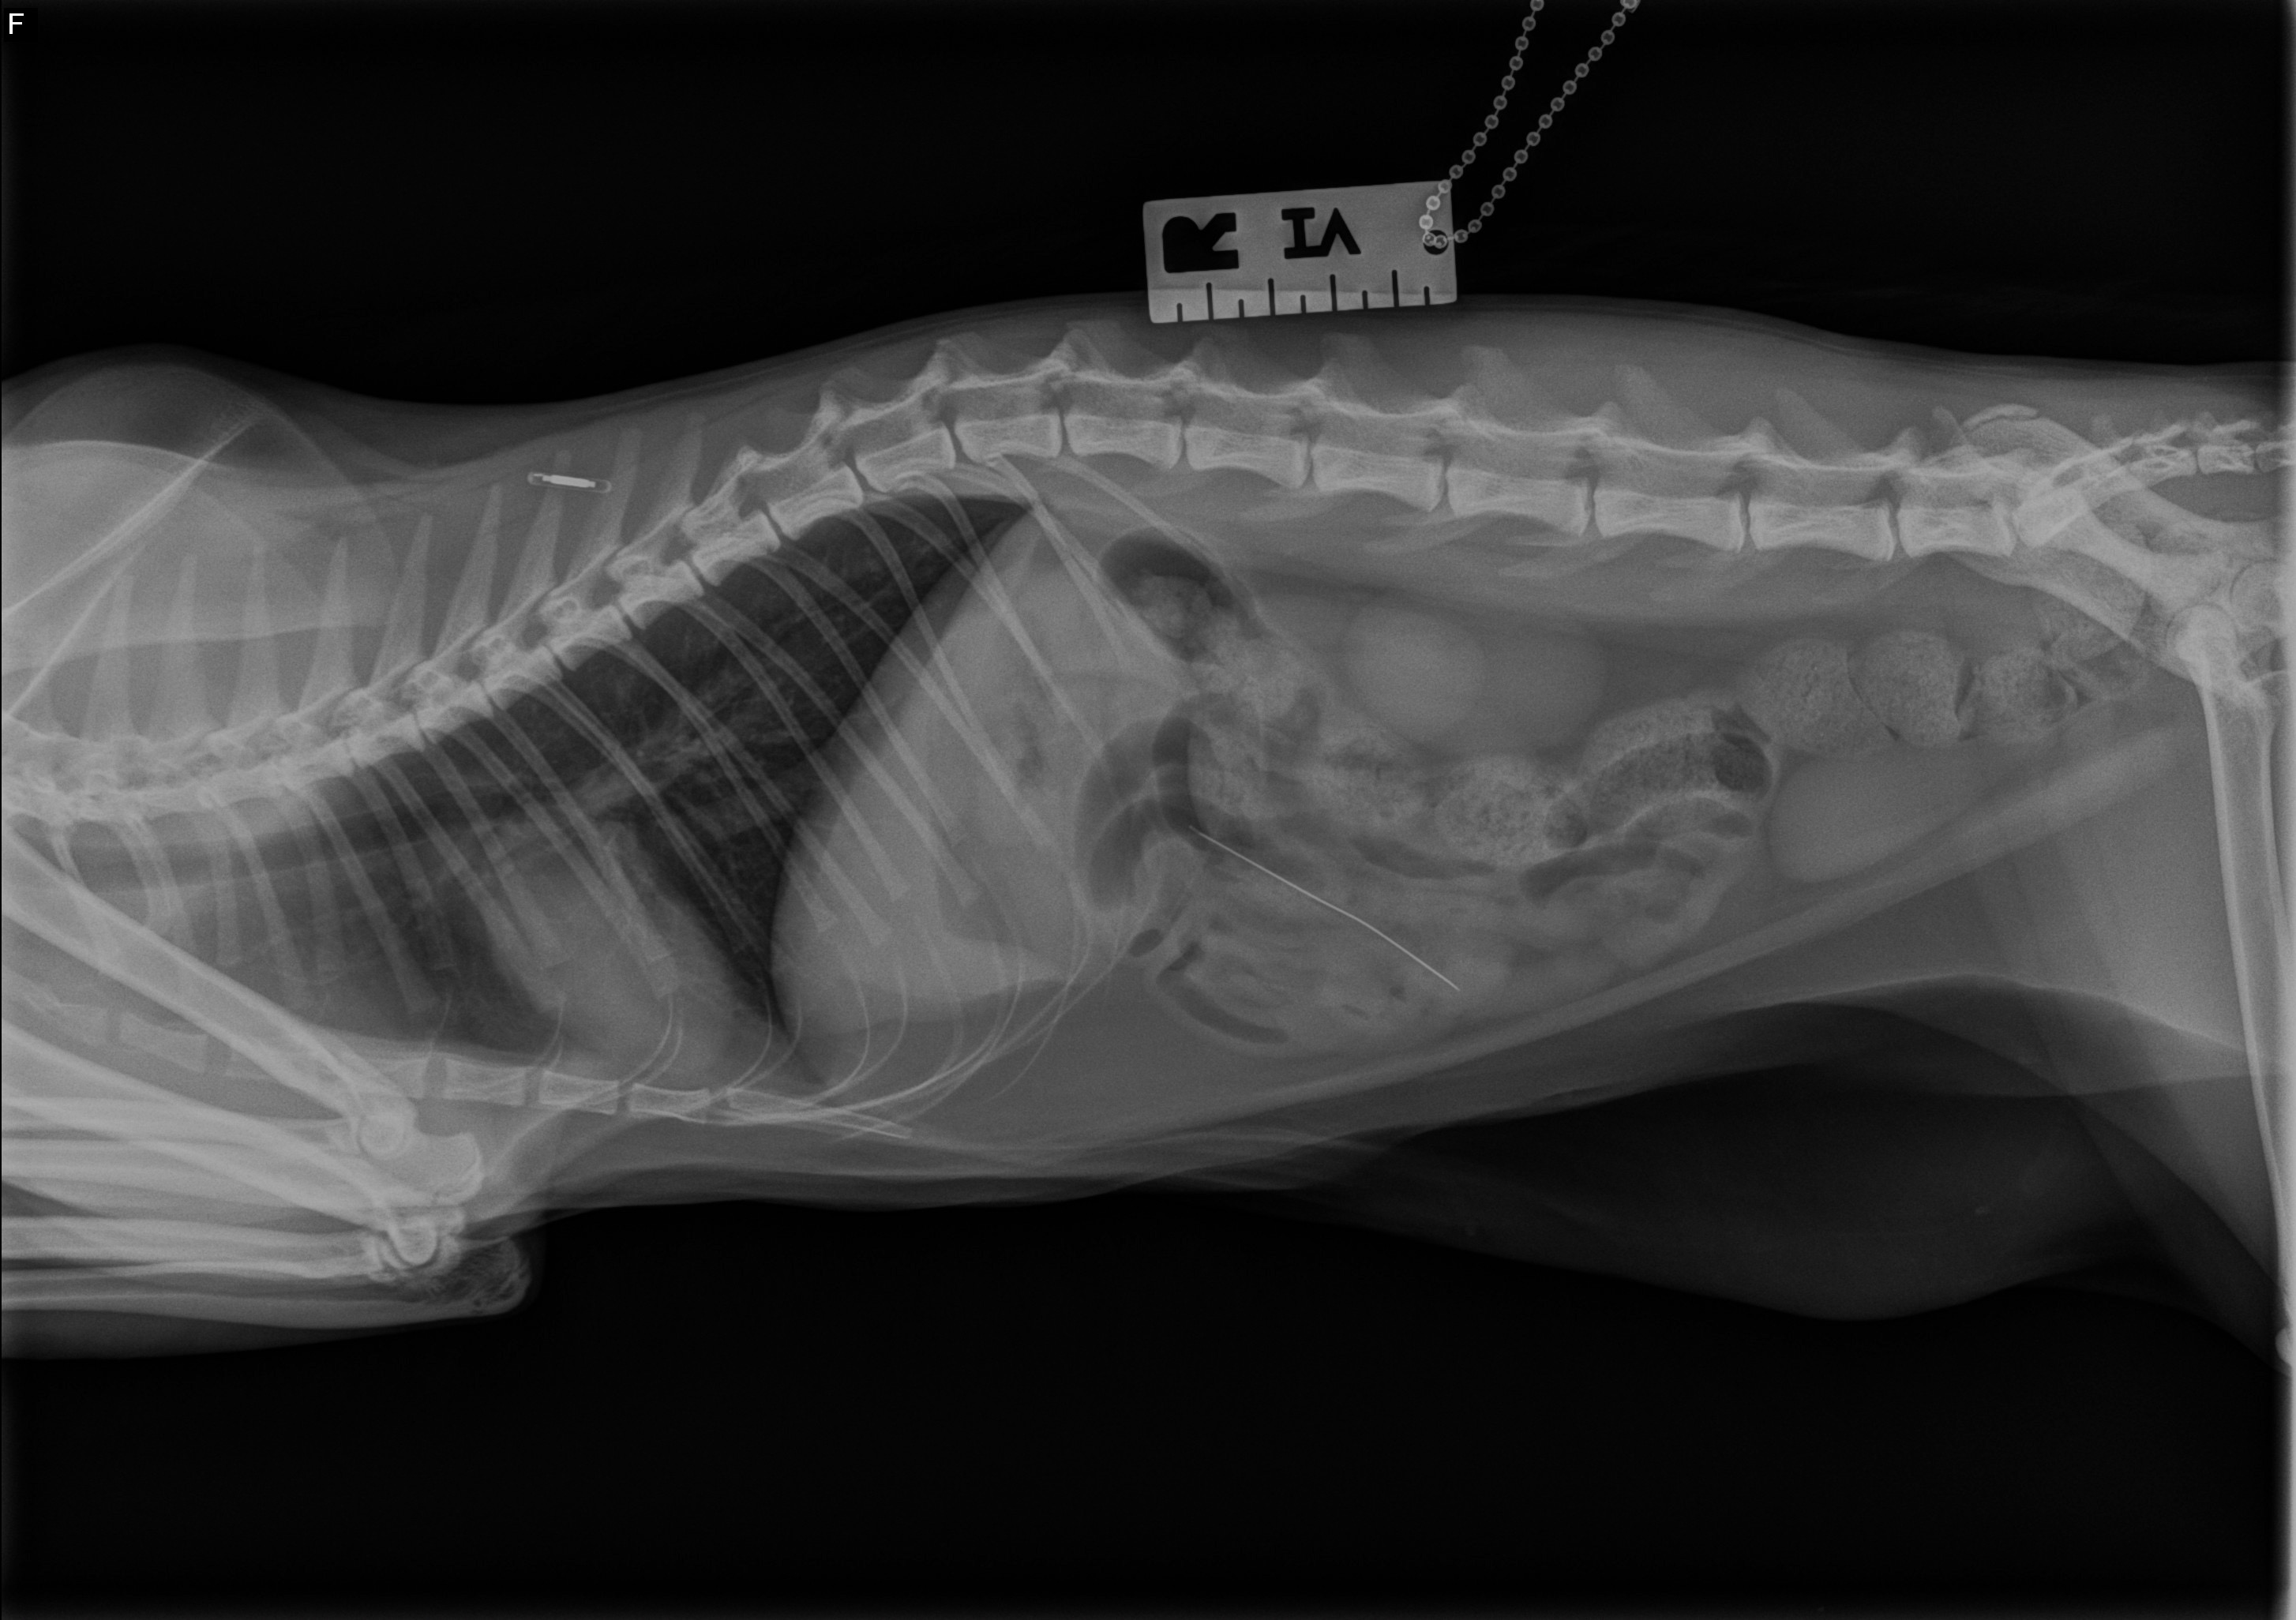

Milo is a one-year-old male cat who recently found himself in a tough situation. He was surrendered by his previous owner after accidentally swallowing a 1.5-inch beading needle. Right now, Milo urgently needs surgery to remove the needle before it causes a blockage or, even worse, perforates his intestine. Without this procedure, his health is at serious risk, and he could face life-threatening complications.